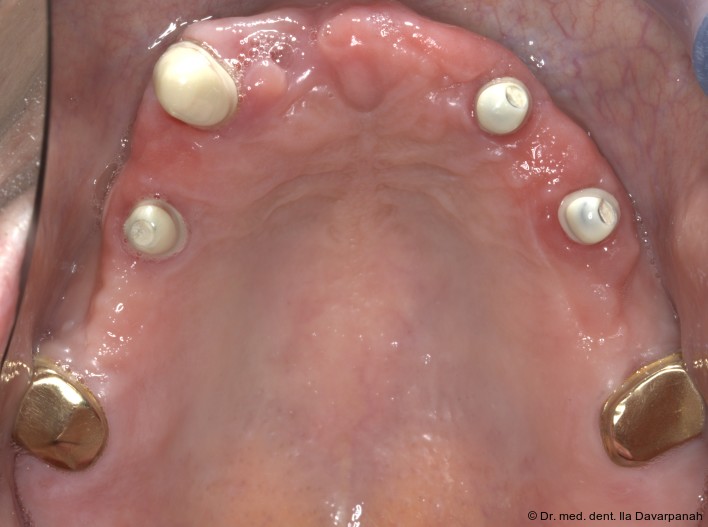

Die Implantation erfolgte navigiert mit einer Bohrschablone. Zur Optimierung der Ästhetik wurden im Frontzahnbereich bewusst keine Implantate gesetzt (Abb. 5). Nach Einheilung und Freilegung der Implantate begann die prothetische Phase (Abb. 6).

Um die primären Teleskope und Reiseprothesen herzustellen wird der Implantat-/Zahnabdruck (Abb. 7, 8, 9) von dem digitalen Abdruck der OK-Prothese in situ, in idealer Kieferrelation überlagert und als Vorlage für die Ästhetik und Okklusion verwendet. Es gilt zu beachten, dass hierfür die vertikale Dimension physiologisch eingestellt sein sollte oder dass es eine Option gibt, die vertikale Dimen­sion aus der vorherigen Situation wiederher­zustellen (Abb. 7–9). Nach der CAD/CAM- basierten Herstellung der Primärteleskope wurden die Zirkonoxid-Primärschalen auf den Abutments verklebt (Abb. 10–12).